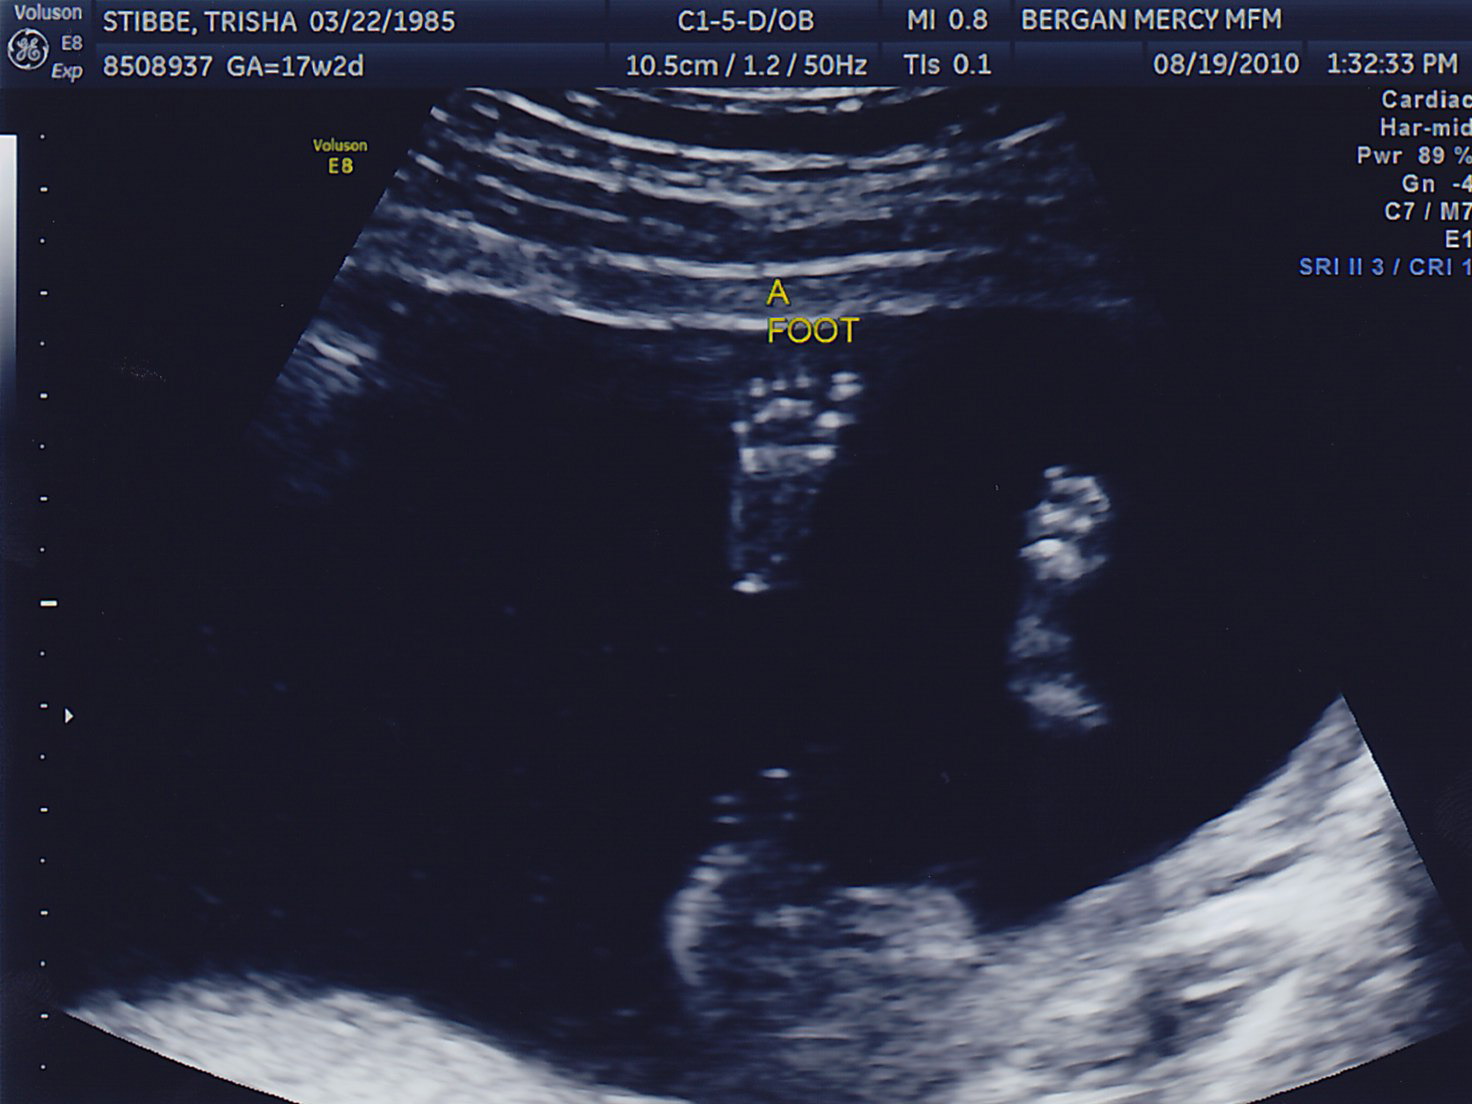

Today was the BIG appointment!!! They were able to confirm that the babies are identical. Yay!

Surprise though… until Adam gets home. We had the ultrasound tech put the pictures in an envelope and Dad hid it so I couldn’t peak. We’ll have the news soon!!! 🙂